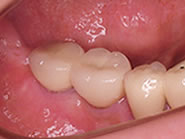

セラミックの歯が入り良く噛めるようになりました

2本の白いセラミック冠が入りました

入れ歯でなく自分の歯と同じように噛めるようになりました